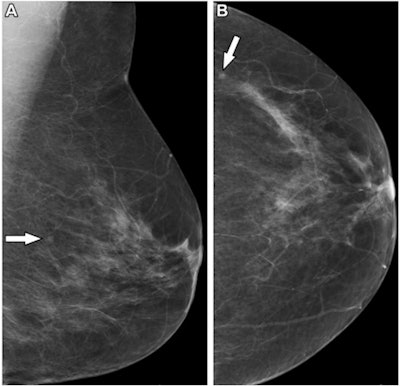

In countries with workforce constraints, could radiographers help with double reading of mammograms? U.K. researchers believe they can, and say their results support the use of physician extenders for breast screening, according to study published on 13 September in Radiology.

A team led by Yan Chen, PhD, associate professor of cancer screening at the University of Nottingham, found no significant differences between radiologists and radiographers for cancer detection rate, recall rates, and positive predictive values.

They looked at data from 401 readers who double-read a total of 1,404,395 screening digital mammograms. The readers included 224 radiologists and 177 radiographers. The study authors measured cancer detection rate, recall rate, and positive predictive value, finding no statistically significant differences between the groups.